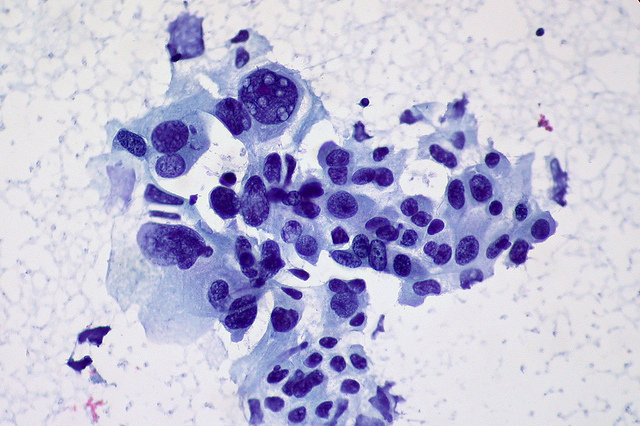

Dass zu viel Arbeit krank machen kann, ist schon lange kein Geheimnis mehr. Eine zu hohe Belastung im Job kann mit erhöhtem Stresslevel, Kopfschmerzen, Schlafproblemen und gar Herz-Kreislauf-Erkrankungen bis hin zum Herzinfarkt einhergehen. Forscher haben nun einen weiteren Zusammenhang entdeckt, und zwar zwischen dauerhaft erhöhtem Arbeitsstress und dem Risiko für Darmkrebs und Speiseröhrenkrebs. Und auch Lungenkrebs scheint bei viel gestressten Menschen öfter aufzutreten – auch dann, wenn man das Risiko durch Rauchen berücksichtigt. Foto: Non-small Cell Carcinoma of the Lung, FNA, Ed Uthman, Flickr, CC BY-SA 2.0 Diverse Faktoren führen zu Krebserkrankungen Krebs gehört weltweit zu den häufigsten Erkrankungen. Was genau die Mutation der Körperzellen auslöst, ist jedoch auch heute nur in Teilen bekannt. Zu den bekannten Einflussfaktoren gehören neben Umwelteinflüssen auch die Ernährung und die Lebensweise. Rauchen und Übergewicht kann das Tumorrisiko erhöhen, aber auch biologische Faktoren wie genetische Veranlagungen oder die Körpergröße nehmen Einfluss auf das individuelle Risiko, an Krebs zu erkranken. Ein Team rund um Tingting Yang vom Volkshospital im chinesischen Henan wollten untersuchen, welchen Einfluss Stress auf das Krebsrisiko hat. Zwar konnten einige Studien bereits Indizien für einen Zusammenhang zwischen Krebserkrankungen und chronischem Stress gefunden, aber bisher war nicht geklärt, ob der Stress selber ein Risikofaktor ist oder mit ihm verbundene Verhaltensweisen wie etwa Rauchen und ungesunde Ernährung. Um dieser Frage nachzugehen, haben die Forscher Gesundheitsdaten von mehr als 280.000 Teilnehmern ausgewertet, die an Langzeitstudien in Nordamerika und Europa teilgenommen haben. Bei ihrer Analyse konzentrierte sich das Team auf Zusammenhänge zwischen dem Stressniveau der Probanden und verschiedenen Krebserkrankungen. Stress fördert das Krebsrisiko Und die Forscher wurden fündig: Bei Darm- und Speiseröhrenkrebs fanden sie eine deutliche Korrelation. Und auch bei Lungenkrebs zeigte sich eine deutliche Häufung bei übermäßig gestressten Menschen. Auch bei der Berücksichtigung anderer Risikofaktoren wie etwa Rauchen, Übergewicht und Lebensweise blieb der Zusammenhang erhalten. Überrascht waren die Forscher jedoch, als sie entdeckten, dass die Frage, für welche Krebsart der Stress anfällig macht, auch vom Wohnort abhängt. „ In Nordamerika war der Effekt des Arbeitsstresses auf den Darmkrebs statistisch signifikant, nicht aber in Europa„, heißt es von Seiten des Teams. In Europa wirkte sich der Stress dagegen vornehmlich auf das Speisröhrenkrebs-Risiko aus. Die Studie der Wissenschaftler zeigt zwar die Korrelationen auf, aber welche Mechanismen hinter diesen und speziell den Unterschied beim Wohnort erklären, wissen die Forscher nicht. „ Es existieren verschiedenen biologische Mechanismen, durch die Stress zu Krebs führen kann„, so Yang. Bei Prostatakrebs, Brustkrebs und Eierstockkrebs fanden die Forscher dagegen keinerlei Zusammenhänge mit dem Stressniveau. Teile den Artikel oder unterstütze uns mit einer Spende. Facebook Facebook Twitter Twitter WhatsApp WhatsApp Email E-Mail Newsletter